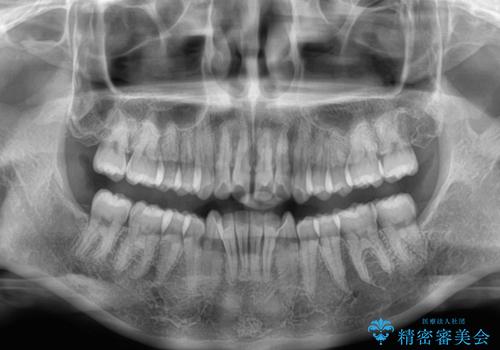

- 上の前歯の隙間を気にして来院された患者様です。

インビザラインにより、上下の歯列を側方に拡大しつつ、前歯の隙間を閉じていくこととしました。

隙間の原因は強い咬合力や舌の突出癖、小帯の異常付着などがありますが、舌のトレーニングをしっかりと行いながら、装着時間を遵守して装着していただいたおかげで、スムーズに治療を終えることができました。